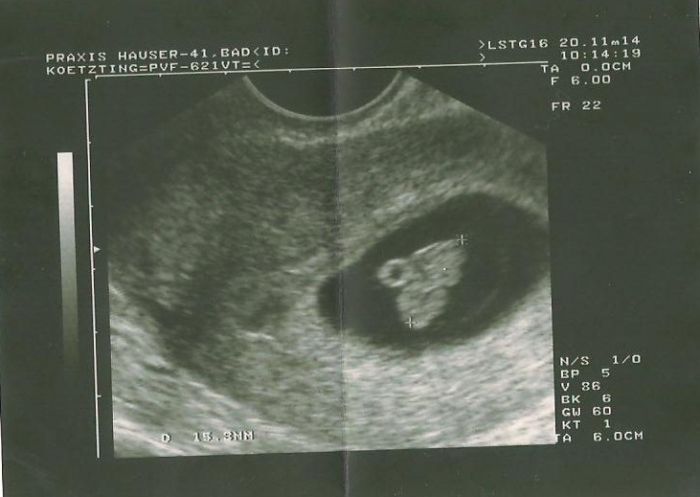

Ahoj, holky.. Chtěla bych se s Váma podělit o mou dnešní radost.. :) Cítím se šťastně..Byla jsem na prohlídce, srdíčko tluče

, velikost sedí, vše je jak má být a já se cítím opravdu šťastně... Pevně věřím, že brzy budete prožívat stejné pocity!!!

Chci snažilky povzbudit, určitě to vyjde..

Je jasné, že do každé prohlídky nějaké obavy budou, to nejde vymazat, ale při každé dobré zprávě budu pociťovat takové štěstí jako dnes...Tady je fotečka mrňouska..